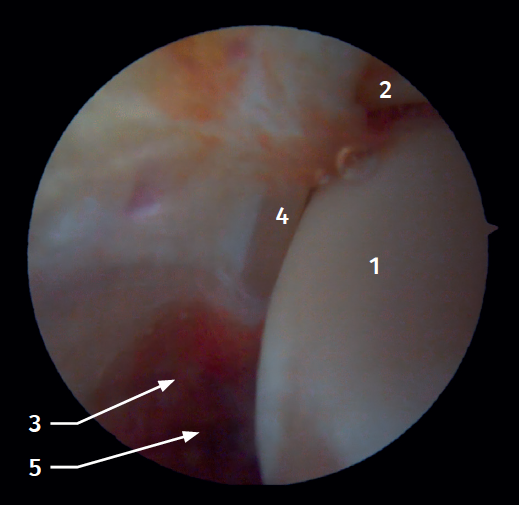

Anterior arthroscopic view

Twenty percent of the ATFL is intra-articular(7). On adopting an anteromedial access of the ankle, directing the arthroscope laterally, we can see the distal fibers of the ATFL with their oblique distribution and their continuation with the anterior talofibular ligament (Figure 2). If we move into the tibiotalar joint, we see the distal tibiofibular joint with the syndesmotic recess occupied by synovial tissue (Figure 3).

Posterior arthroscopic view

From the posterolateral approach we identify the lateral (fibular) malleolus and, from here, we visualize the intra-articular fibers of the PTFL, which run obliquely and insert into the distal portion of the tibia. We also see the distal thickening of the PTFL (transverse ligament) in continuity with the posterior lip of the distal tibia (Figure 4).